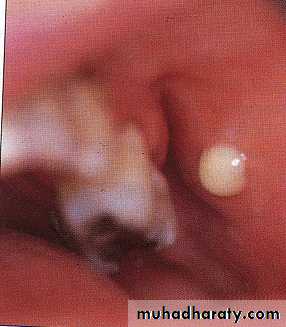

• Mainly occur in parotid gland• Acute ulcerative papillary obstruction

• Occurs as a result of an ulcer in papillae which cause obstruction of parotid gland .

• Etiological factor is trauma

• Rx :removal of the causative agent the condition subside by it self when the ulcer is heal